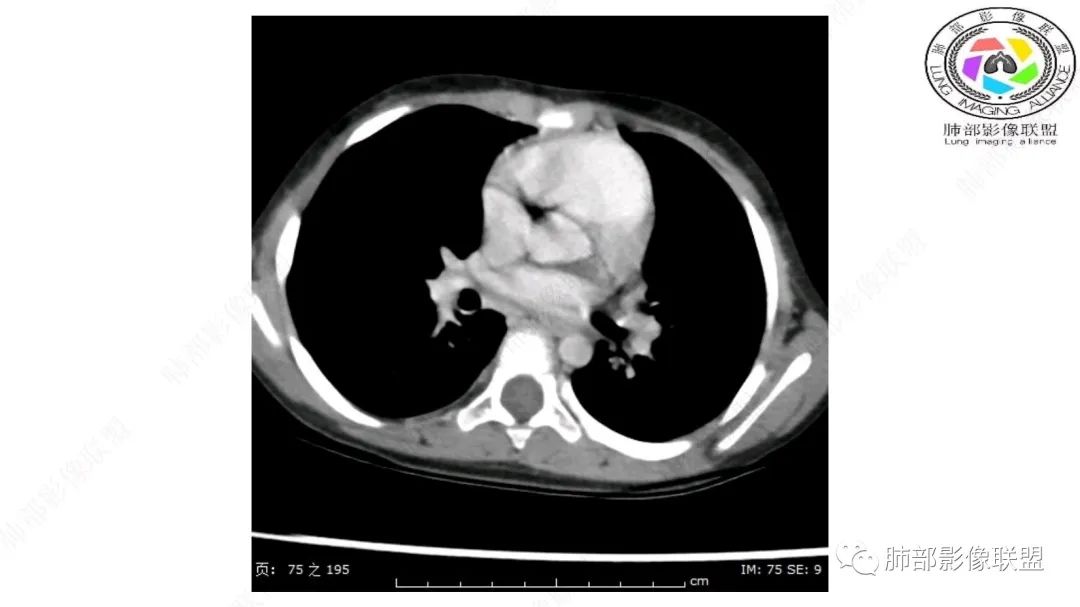

右上纵隔混杂密度肿块,边缘光整,与纵隔分界清,其内多发脂肪密度,增强无明显强化,其内血管穿行,考虑纵隔脂肪母细胞瘤,鉴别畸胎瘤,脂肪肉瘤。

右纵隔团状,密度不均,脂肪密度为主,内可见腺体样组织,类似乳腺,病灶边缘有分叶,与胸腺关系密切,增强后血管穿行。考虑胸腺脂肪瘤(不典型垂乳征),鉴别畸胎瘤。

3岁儿童,右纵隔占位,内部间多发脂质成分及斑片状稍高密度影,考虑纤维成分,增强似有强化。病灶内血管未见明显侵犯,可考虑脂肪母细胞瘤,冬眠瘤等。

三岁小儿,右侧纵隔巨大脂肪密度肿块,肺动脉穿行其中,密度欠均匀,未见明确实性成分,纵隔脂肪母细胞瘤,冬眠瘤鉴别纵隔脂肪增多症(多弥漫对称)。

患儿3岁 咳嗽检查发现纵隔占位。右肺上叶受压表现,占位以脂肪组织密度为主,似见分隔,首先考虑为脂肪母细胞瘤,鉴别脂肪瘤,畸胎瘤。

幼儿,右上纵隔团块状脂肪密度影,边缘清晰,内可见血管及支气管穿行,考虑脂肪瘤,鉴别畸胎瘤。

幼儿,右上纵膈团块,脂肪密度,内见分隔,增强病灶内见血管穿行,结合患者年龄,考虑脂肪母细胞瘤,鉴别脂肪瘤。

纵隔畸胎瘤,右前上纵隔团状脂肪密度?粘液样密度为主病变,病灶软边缘有分叶,内可见分隔,增强后血管穿行。3岁。考虑纵隔脂肪母细胞瘤,鉴别畸胎瘤。

定位肺外纵隔内,脂肪密度,内可见纤维分割,3岁,脂肪母,鉴别畸胎瘤。

右上纵膈混杂密度肿块,边缘光整,与纵膈分界清,其内多发脂肪密度,增强无明显强化,其内血管穿行,考虑纵膈脂肪母细胞瘤,鉴别畸胎瘤,脂肪肉瘤。

定位:肺内?尖段气管未见明显显示,腔静脉受压向右推移?病灶内可见前段动脉穿行,脂肪密度为主。

肿块起源于右上气管分叉处?强化动脉血管最后汇入右肺动脉上干。

右侧纵隔奇静脉水平起源?压迫上肺,包绕动脉?

小儿,右上纵隔占位,脂肪密度,血管未见破坏,考虑胸腺脂肪瘤,畸胎瘤。

右肺门上方,位于纵隔胸膜旁见巨大肿块,脂肪为主混合密度,内见细小血管影,肿块最大长径与纵隔胸膜平行,包绕右肺上叶肺动脉,右肺上叶及纵隔结构推压,无侵蚀破坏,良性肿瘤,起源纵隔胸膜血管平滑脂脂肪瘤。

跨肺门,包绕肺血管分支,邻近肺组织受压肺不张。

可以看到造影剂进入的丛状结构

密度不均,非纯脂肪成分。斑片状密度略高区域有轻度填充式强化。

婴幼儿,病变较大,跨肺门,分叶,富含纤维或黏液、含成熟脂肪,破坏力弱或无,浸润性生长模式不明显,未见远处转移。

综合:富含成熟脂肪的、可以有丛状结构的,可以有纤维或黏液的良性或低度恶性肿瘤。常见疾病谱:脂肪瘤、神经纤维瘤样错构瘤、冬眠瘤、血管脂肪瘤、髓脂肪瘤、脂肪母细胞瘤、黏液样脂肪肉瘤。

鉴别要点:病变成分不单一,非包绕神经结构、间质血管不显著、婴幼儿,良性或低度恶性。

第一个问题:定位:肺内?纵隔?

病灶属于交界区,主体位于肺内,占位效应明显,前方突入胸壁,胸腺受压变形,胸膜显示欠清楚;病灶包绕上叶肺动脉;似乎有体动脉供血。符合肺内的点:包绕上叶肺动脉分支;符合纵隔的点:前方似乎突入胸壁,与胸腺关系比较密切,但是与上腔静脉的关系提示病灶不支持纵隔来源,前纵隔的常规会将上腔静脉受压后移、外移,这是不符合的。

从这个角度符合肺内的,有一点不太踏实的是:似乎突入前胸壁。

手术记录:见右肺上叶肿物,肿物与右肺上叶关系密切。与纵隔无粘连,逐步分离肿物,见肿物大小约6cm*5cm,边界清楚,于右肺上叶粘连,边界清楚,肿物包绕右肺上叶血管及支气管。超声刀逐步游离肿物,完整切除肿物,右肺上叶肺组织无破溃,表面无出血。

1.右上肺-纵隔交界区巨块影,主体位于右肺一侧,紧贴胸腺、头臂干、右锁骨下动脉、上腔静脉、奇静脉等,不能分离,但病灶整体边界清楚。注意上述相邻腔静脉等结构未见受压变形,纵隔亦未见明显向左推移,至少提示两点:

2.肺动脉穿行也许是肺内来源最重要支持点!

CT扫描对脂肪类肿瘤常有独到价值。肿块孤立、边界清楚,未见周围浸润,较均匀脂肪样低密度,高度提示为良性!

发生于成人为脂肪瘤表现,婴幼儿自然会想到脂肪母细胞瘤。两者生物学行为并无本质区别。

脂肪母细胞瘤由成熟程度不同的脂肪组织、纤维间隔、黏液基质、小血管丛等间质成分组成,以脂肪组织与黏液样基质为主,其影像学表现取决于上述组织成分。典型的CT和MRI表现为:前后纵隔均可发生,常见于前纵隔;肿块大小不一,直径多在3cm~7cm,密度均匀,CT值呈水样或脂肪密度,脂肪组织密度或信号为主的肿块,其内密度或信号不均匀,可见粗细不一的分隔影,且有结节、片状影,后者可呈轻中度强化;结节状肿瘤包膜完整;弥漫性者包膜不明显,常呈浸润性生长;周围结构为受压和推移改变,可有少量胸腔积液,淋巴结无增大。